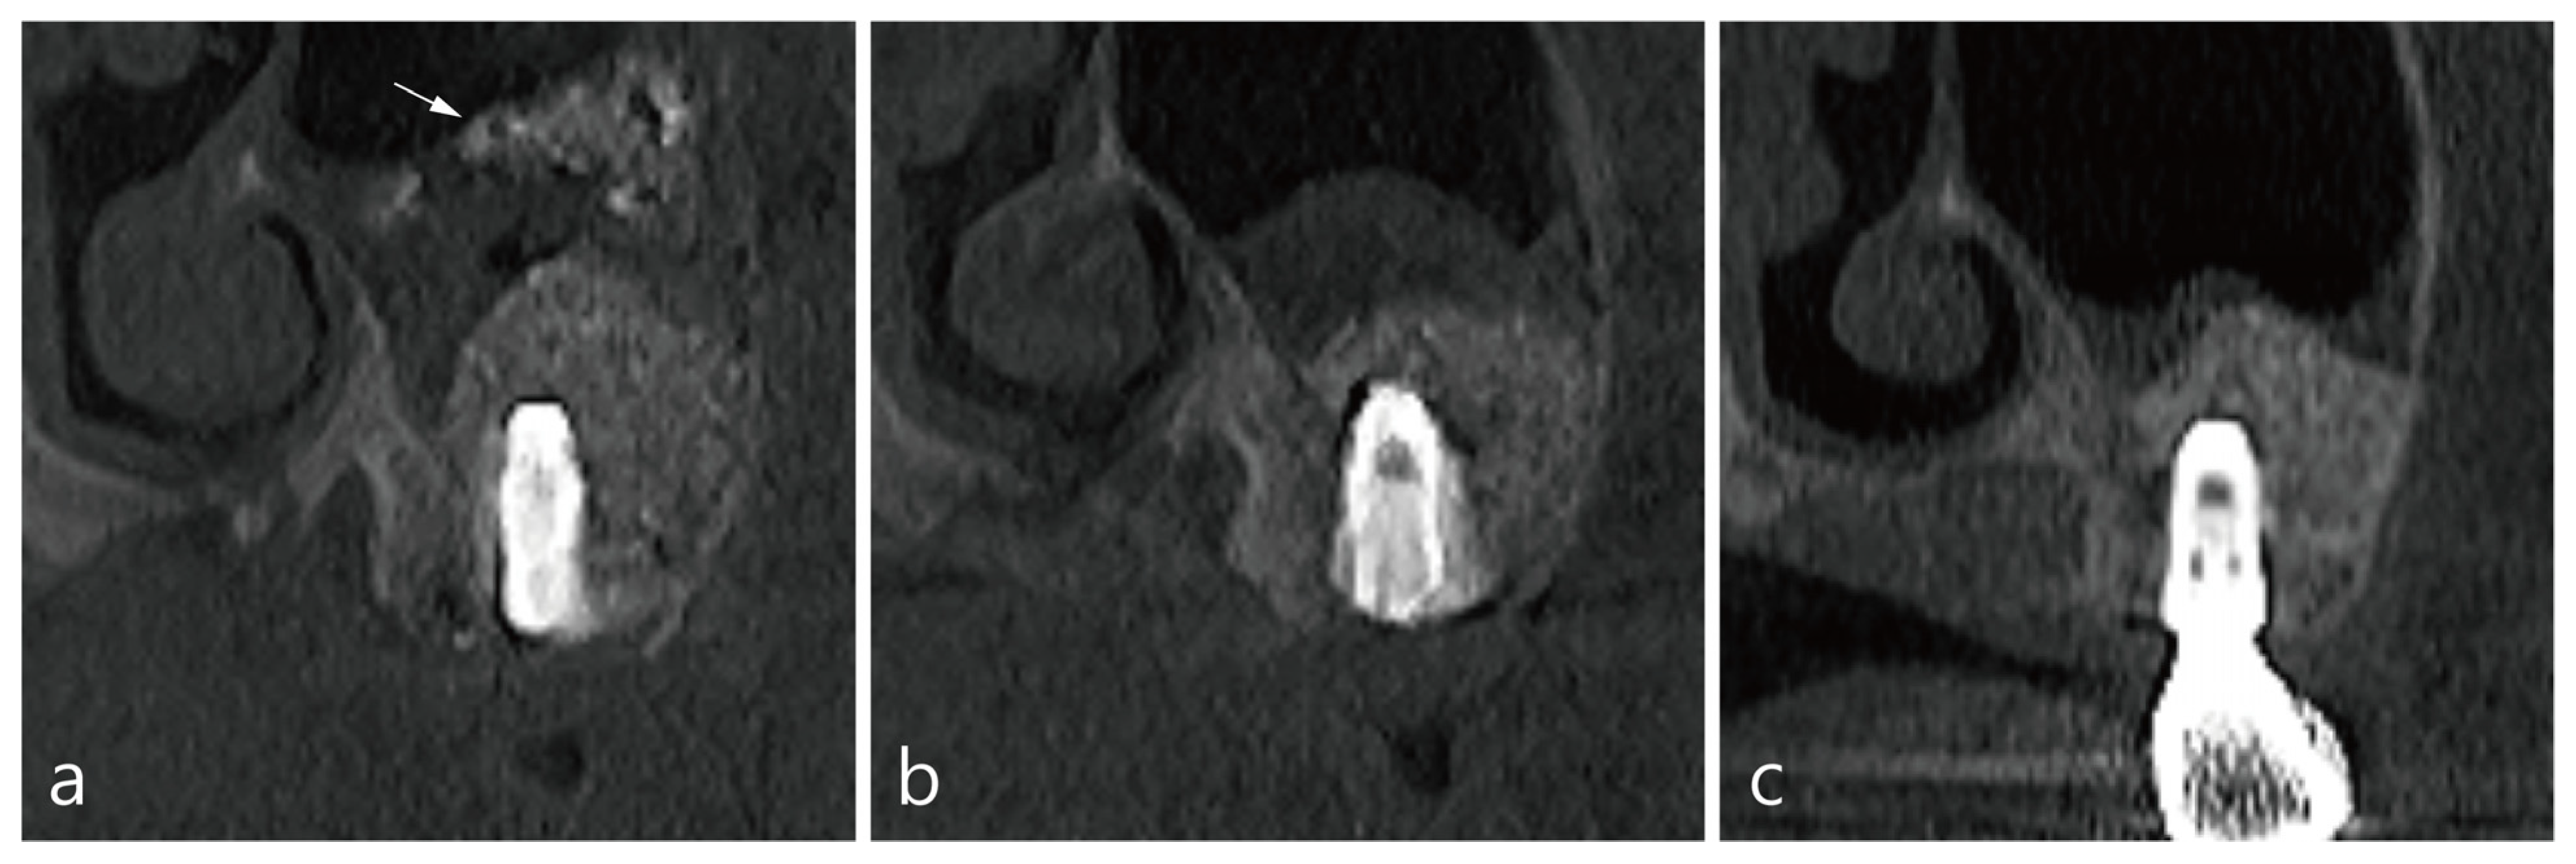

3. Case 1